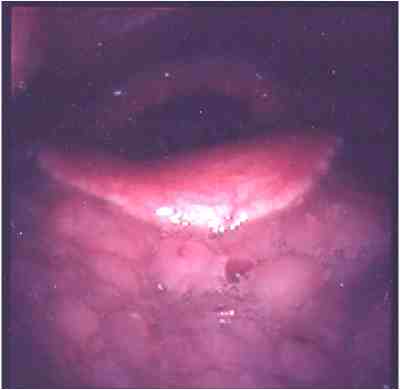

閉塞型睡眠時無呼吸症候群(OSAS)の閉塞部位はどこ?

また,原因となる疾患にはどんなものがあるの?

(OSASは気道の閉塞が原因ですから、気道を狭くする疾患が隠されています。) 睡眠時無呼吸症候群の診断はどうやってするの?